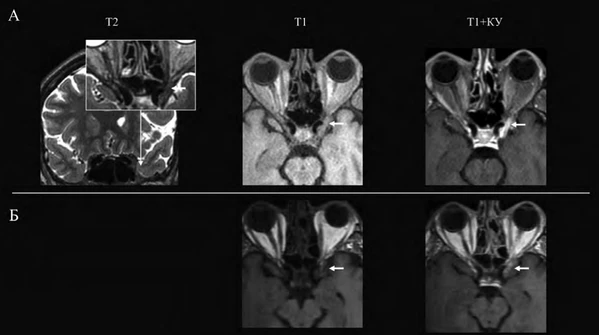

- Магнитно-резонансная томография. Характерны увеличение и выпуклость твёрдой мозговой оболочки; патологическая ткань, накапливающая контрастное вещество; локальное сужение кавернозного сегмента внутренней сонной артерии. Возможно распространение процесса на ипсилатеральную верхушку орбиты, клиновидный синус или среднюю черепную ямку[5].